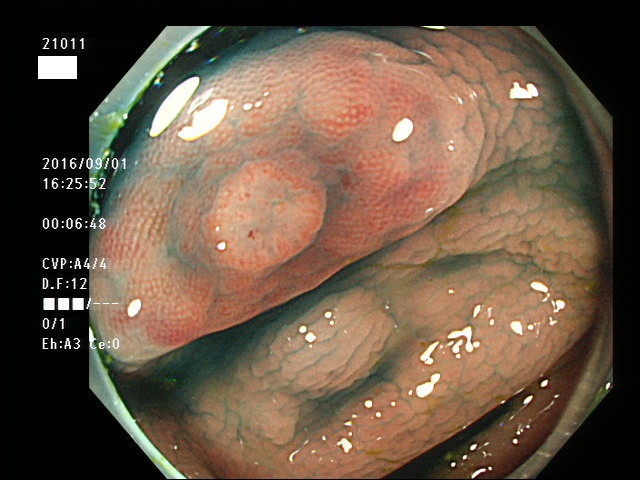

回盲弁(小腸と盲腸の境界)や、憩室の中、炎症で腫れた部位などは複雑に凸凹しており、ここに微小な病変、平坦な病変があると認識が困難になり見落としの危険が高くなります

| 炎症性の隆起(腫れ)の上に発生した腺腫 | 回盲弁上に発生した腺腫(高度異型) |

| 回盲弁上に発生した腺腫(柔毛と区別しにくい) |